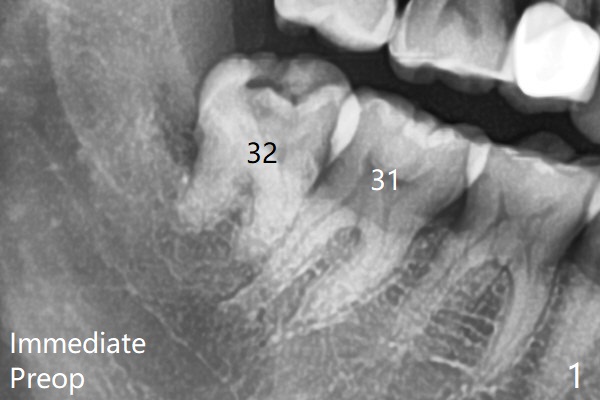

There is limited bone between the lower 2nd and 3rd molars (Fig.1).  Purchase point is made buccal to #17 for elevation.